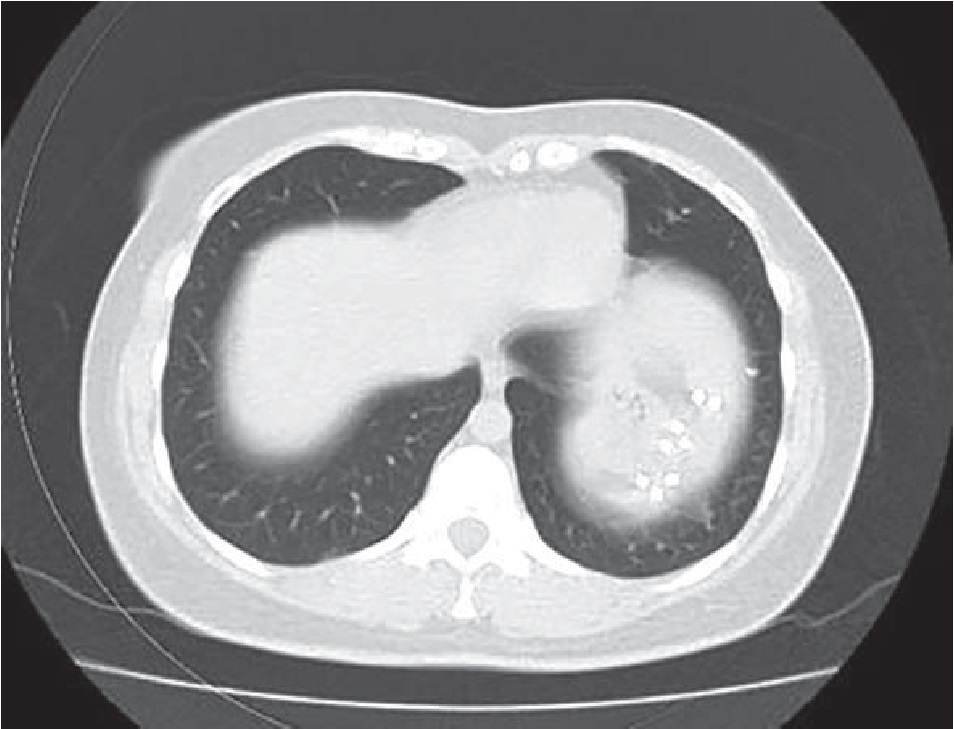

Рис. 3. МСКТ-снимок области диафрагмы спустя 1 месяц после операции

Амбулаторно через 1 месяц после операции выполнена контрольная МСКТ органов грудной клетки и брюшной полости. На ней в проекции левого купола диафрагмы визуализируются скрепки, фиксирующие сетчатый эндопротез. Дефектов купола диафрагмы как слева, так и справа нет (рис. 3).